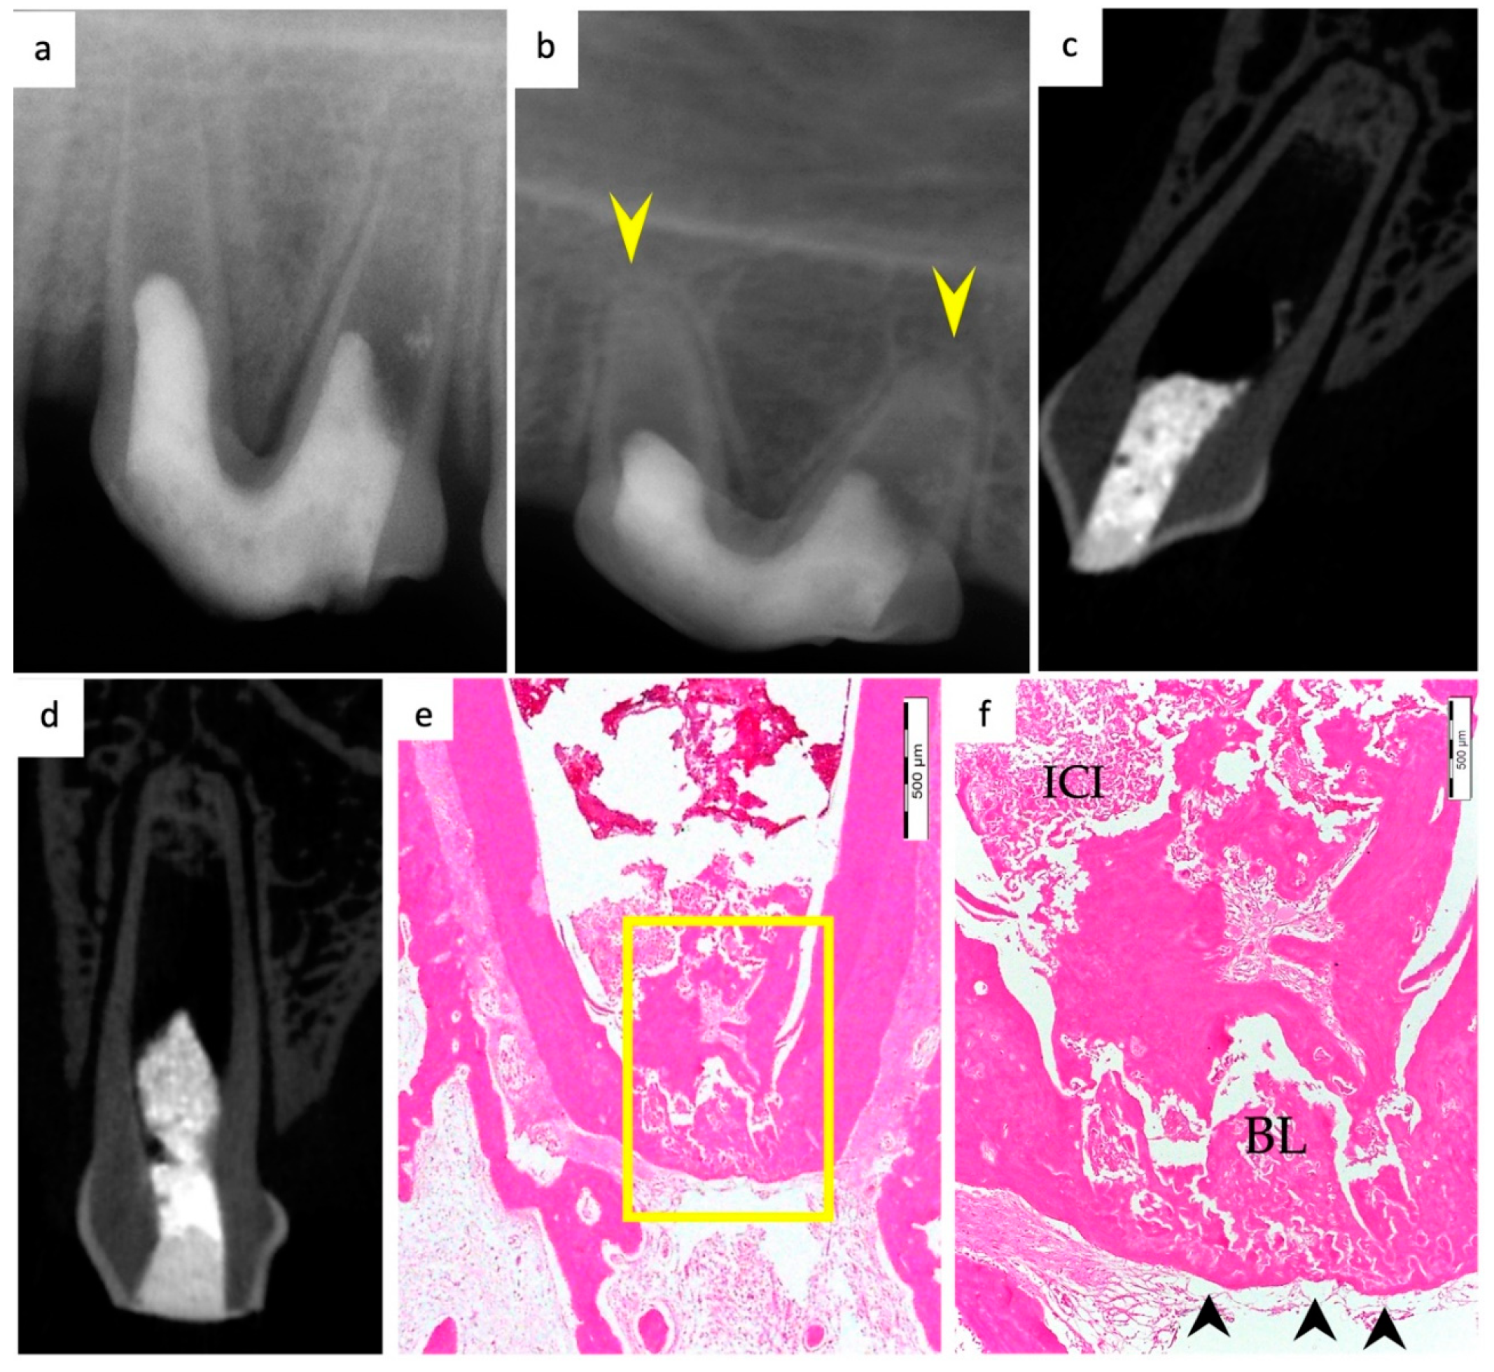

3.1. Hard Tissue Deposition

3.2. Type of Hard Tissue Formed

3.5. Apical Closure

3.6. Positive and Negative Control Groups